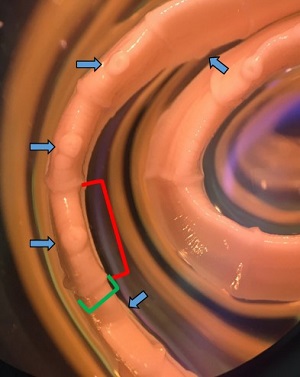

Case #489 – April, 2019

A teenage female college student from Texas observed a foreign object in her feces and took it to her school health clinic. She had no complaints of illness and did not present with any clinical symptoms. She also did not report any domestic or foreign travel history. The specimen was sent to the state public health laboratory for examination. Stool samples were ordered and tested by the school health clinic but the results were all negative for ova and parasites (O&P). The state lab then sent images of the foreign object as well as the physical specimen to the CDC for identification. Figures A and B show what the student observed in her stool. What test method would be useful in identifying the object? What is your diagnosis? Based on what criteria?

Figure A